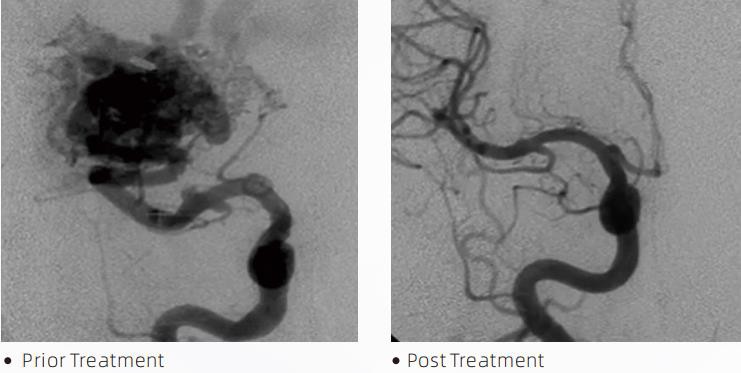

LavaTMLiquid Embolic System este o terapie endovasculară intervențională pentru tratamentul malformațiilor cerebrovasculare. Malformația cerebrală se referă la un grup de anomalii neurovasculare benigne sau maligne care pot duce la hemoragie intracraniană, infarct cerebral, ischemie cerebrală și alte boli. Sistemul de embolizare lichidă este un dispozitiv medical administrat prin inserție intravasculară simplă, care embolizează vasele de sânge cerebrale anormale prin injectarea unui material fluid special. Materialul fluid formează o embolie tisulară controlată în vasele de sânge, care poate reduce impactul malformațiilor cerebrovasculare asupra pacienților. Un microcateter de livrare compatibil cu DMSO care este indicat pentru utilizare în neurovasculatură este utilizat pentru a accesa locul de embolizare. Agentul embolic lichid Lava este un sistem de agent embolic lichid neadeziv format din copolimer EVOH (etilen vinil alcool) dizolvat în DMSO (dimetil sulfoxid) și pulbere de tantal micronizată în suspensie pentru a oferi contrast pentru vizualizare sub fluoroscopie. LavăTMeste disponibil în trei formulări de produse, LAVA-12, LAVA-18 și LAVA-34. LAVA-12: Recomandat atunci când hrăniți microvasele distale și prin hrănitori mici. LAVA-18: Recomandat atunci când hrănirea injecțiilor pediculare vor fi efectuate aproape de nidus; LAVA-34: Recomandat pentru embolizarea debitului mai mare și a componentelor fistuloase mai mari.